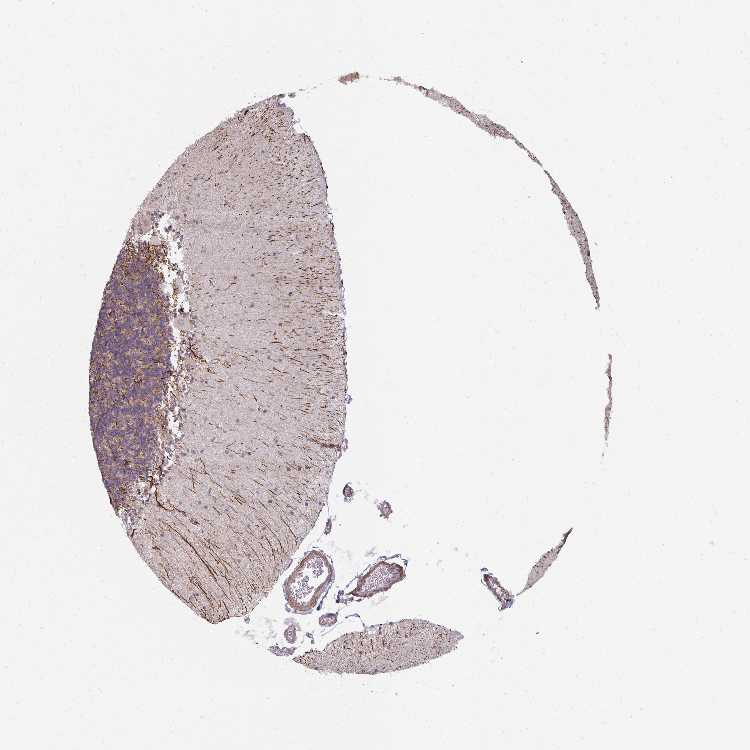

CEREBELLUM - Antibody stainingi

Antibody staining in the annotated cell types in the current human tissue is reported as not detected, low, medium, or high, based on conventional immunohistochemistry profiling in selected tissues. This score is based on the combination of the staining intensity and fraction of stained cells.

Each image is clickable and will lead to virtual microscopy that enables deeper exploration of all samples and also displays staining intensity scores, fraction scores and subcellular localization as well as patient and tissue information for each sample.

Antibody HPA040152

Purkinje cells Not detected

Cells in granular layer Not detected

Cells in molecular layer Not detected